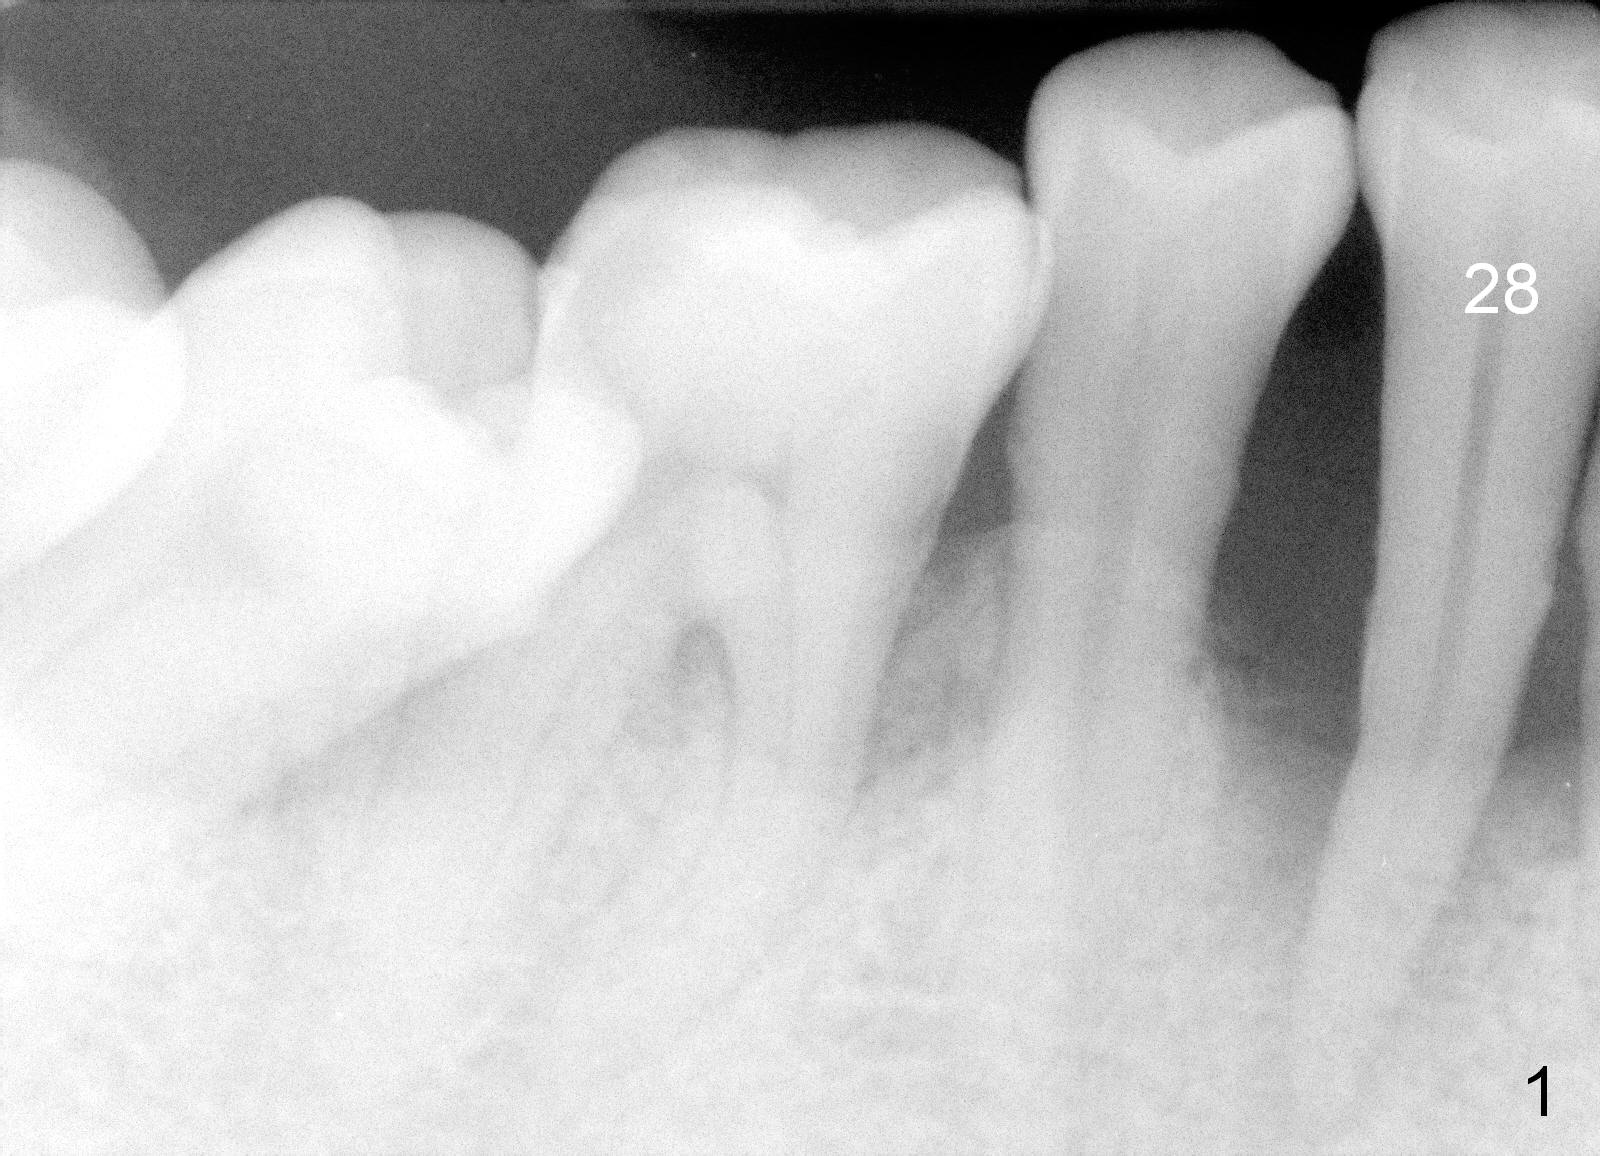

A 62-year-old man (CZ) has severe generalizd chronic periodontitis and occlusal trauma. Full mouth extraction and reconstruction is required. The patient prefers extraction by stage. The lower anterior segment reconstruction is our first treatment: from #22-28. The tooth #28 is exfoliated now (Fig.1 (full mouth X-ray was taken 4 years ago), 5). There are 3 incisors left. Two-piece implants are going to be placed for the canines and premolar, while 2 of 1 piece implants in the incisor sockets (treated with Metronidazole with Epinephrine gauze) for a bridge (Fig.2). Straight 1 piece 3 mm implants are routinely placed, whereas angled or 2.5 mm ones are backup. Two of 1.2 mm pilot drills and 3 of marked parallel pins may be needed.

The waxed-up tooth at #28 appears to be too wide, probably due to mesial shifting of the anterior tooth (Fig.6). An implant will be placed at #28 prior to anterior tooth extraction so that the neighboring teeth will be used as trajectory guides. It will be placed as distal and lingual as possible. Surgical and restorative stents have been fabricated with change into normal overbite (Fig.6,7 red line).